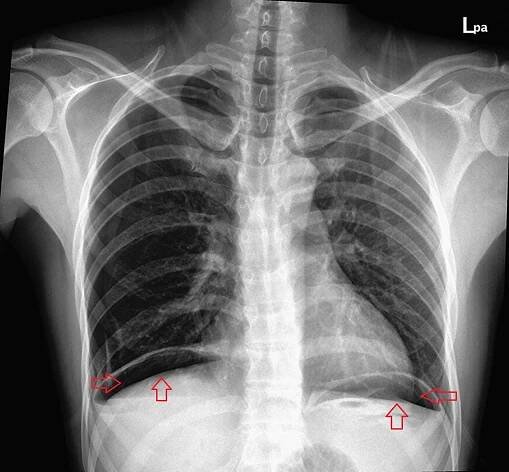

Double wall sign. This is a secondary sign of pneumoperitoneum. Patient is supine, and air within the abdomen and lumen of the bowel accentuate both sides of the bowel wall.